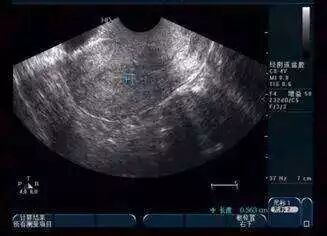

排卵监测有很多种,但“超声监测排卵”是公认最准确的方法。一般情况,每个月最终会有1或2颗卵子排出,但其实每个月都有很多卵泡在发育,经过激烈的竞争,只有一颗或两颗卵泡能够胜出。这一两颗卵泡就是我们说的“优势卵泡”。

其实在月经结束后的三四天,究竟哪个是优势卵泡就可初见端倪。因此通常会建议,在月经开始后的9~10天进行第一次超声监测,看看有没有优势卵泡以及它的大小。

此后每1~3天复查一次超声,了解了解优势卵泡的生长情况,当优势卵泡平均直径接近18mm时可指导夫妻隔日安排同房。

但一定注意,超声要持续追踪到排卵结束。如果卵泡持续生长,有不排卵,黄素化的趋势,可注射HCG促进卵泡排出。